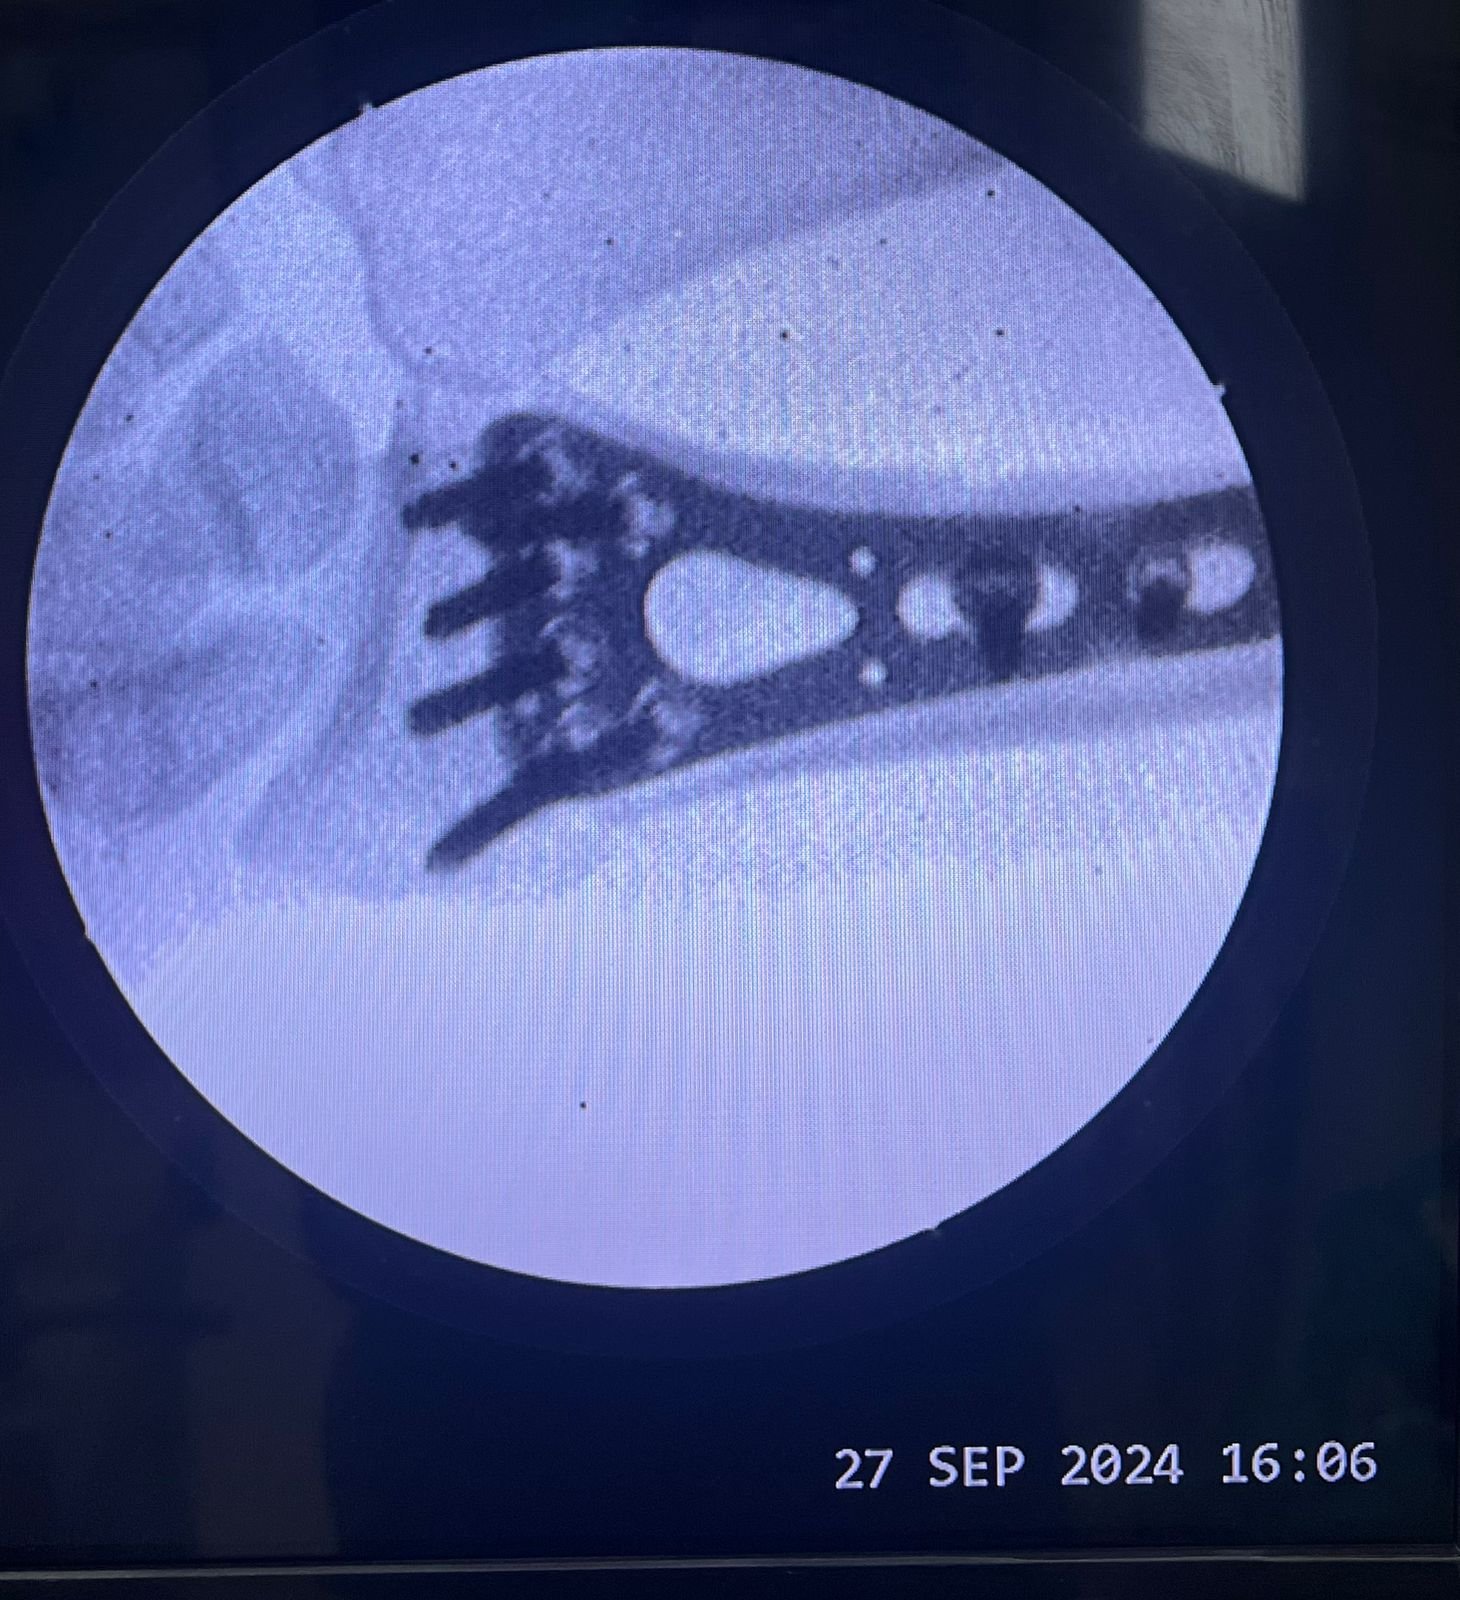

Pre op & postop X-ray compound fracture lower tibia

& fibula | Heal fracture pre & postop | Clavicle